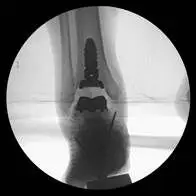

These are pics of the fusion prior to takedown